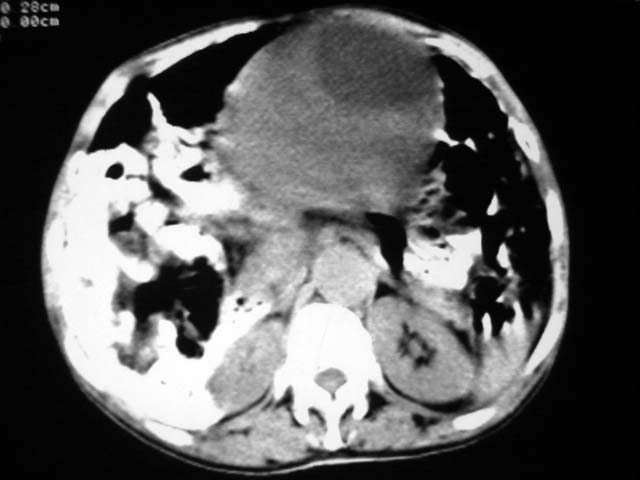

女,75岁,腹部胀大半年余,无其他症状。

考虑来源与卵巢的巨大囊腺瘤或囊肿。

考虑来源于卵巢的巨大囊腺瘤;如果是单纯囊肿不知其前部的更低密度区怎么解释?

考虑来源卵巢巨大黏液性囊腺瘤。